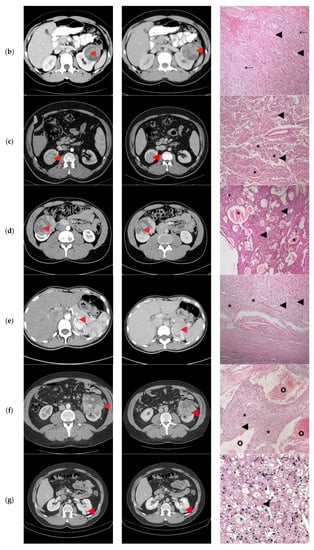

None of the patients had tumor invasion of the renal vein or the adjacent organs, calcifications, or macroscopic fat (Figure 2).

Figure 2.

Computer tomography findings in the cortico-medullary and nephrographic phases; Histopathological examination (a) Heterogeneous peripheral contrast enhancement, like the renal cortex (◄); Clear Cell RCC, Fuhrman grade 2. Tumor with compact and alveolar architecture (◄) of cells with clear cytoplasm, distinct cell boundaries and nuclei with nucleoli prominent at 100×. (b) Moderate nodular enhancement (◄); Clear Cell RCC, Fuhrman grade 1. Tumor with alveolar (←) and tubular architecture (◄) of cells with clear cytoplasm, distinct cell boundaries and nuclei with inconspicuous nucleoli at 100×. (c) Faint intra-tumoral contrast enhancement with mild progression in the nephrographic phase (◄); Papillary-RCC, type II. Tumor with papillary architecture (*) with pseudostratified layers (◄) of large cells with abundant eosinophilic cytoplasm, atypical nuclei with prominent nucleoli at 100×. (d) Heterogeneous contrast enhancement, less than the renal cortex in both phases, with an important necrotic component (◄); Adult cystic nephroma. A tumor composed of various sized cysts (◄) lined by flat cells separated by fibrous septa that contain smooth muscle (*) at 100×. (e) Intense contrast in the cortico-medullary phase, with an apparent central “scar” (◄) and less contrast enhancement compared to the renal cortex in the nephrographic phase; Clear Cell RCC, Fuhrman grade 1. Tumor with alveolar (*) and tubular (◄) architecture of cells with clear cytoplasm, distinct cell boundaries, and nuclei with inconspicuous nucleoli at 100×. (f) Bulky exophytic tumor with nodular peripheral contrast enhancement, like the renal cortex on the cortico-medullary phase and less than this on the nephrographic phase (◄); Clear Cell RCC, Fuhrman grade 2. Tumor with alveolar (*), tubular (◄) and cystic (o) architecture of cells with clear cytoplasm, distinct cell boundaries, and nuclei with nucleoli prominent at 100×. (g) Peripheral contrast enhancement like the renal cortex with an apparent “central scar” (◄) on the cortico-medullary phase and wash-out on the nephrographic phase, with the persistence of the “central scar”; Multicentric Chromophobe-RCC. Flocculent cytoplasm that condenses around the edges (“plant cell-like”, ◄) and pleomorphic nuclei (←) at 400×. (h) Faint peripheral enhancement on both phases (◄); Clear Cell RCC, Fuhrman grade 1. Tumor with the alveolar architecture of cells with clear cytoplasm (*), distinct cell boundaries (←), and nuclei with inconspicuous nucleoli at 100×. (i) Bulky tumor with peripheral enhancement (◄), like the renal cortex in the cortico-medullary phase, with progressive filling in the nephrographic phase; Clear Cell RCC, Fuhrman grade 2. Tumor with alveolar architecture (*) of cells with clear cytoplasm, distinct cell boundaries and nuclei with nucleoli prominent at 100×. (j) Faint spotted intra-tumoral enhancement on both phases (◄); Multiloculated cystic RCC, Fuhrman grade 1. Tumor with cystic architecture (*), with thin fibrous septae (◄) lined by clear cells (←). Tumor cells with inconspicuous nucleoli at 100×. (k) Faint, spotted intra-tumoral enhancement on both phases (◄); Metanephric adenofibroma. A tumor composed mainly of tightly packed tubules (◄) and secondarily long branching and angulated ducts (←). Tumor cells have scant cytoplasm and nuclei are small with no nucleoli, with no mitotic figures. Stroma is present as significant fibrous septa (*) at 100×. (l) Peripheral enhancement is like the renal cortex with the presence of a central non-enhancing area (“central scar”) (◄), on both phases; Oncocytoma. Small oncocytic cells (◄) with round, regular nuclei, no mitosis at 200×. (m) Peripheral enhancement like the renal cortex on the cortico-medullary phase and discretely less than the renal cortex on the nephrographic phase (◄); Clear Cell RCC, Fuhrman grade 1. Tumor with alveolar architecture (*) of cells with clear cytoplasm, distinct cell boundaries, and nuclei with inconspicuous nucleoli. The tumor invades a segmental renal vein (◄) at 100×. (n) Discrete nodular, peripheral enhancement (◄), less than the renal cortex on both phases; Papillary RCC, type I. Tumor composed of small cuboidal cells, with scant cytoplasm and round nuclei without nucleoli, arranged on a single layer on papillary cores (◄). Some of the papillary cores contain foamy macrophages (←) at 100×. (o) Peripheral enhancement less than the renal cortex on both phases (◄); Clear Cell RCC, Fuhrman grade 1. Tumor with a compact and alveolar architecture of cells with clear cytoplasm (←), distinct cell boundaries, and nuclei with inconspicuous nucleoli at 100×. (p) Bulky tumor with peripheral enhancement, less than the renal cortex on both phases (◄), with wash-out in the nephrographic phase; Clear Cell RCC, Fuhrman grade 1. Tumor with alveolar architecture (*) of cells with clear cytoplasm, distinct cell boundaries, and nuclei with inconspicuous nucleoli at 100×.